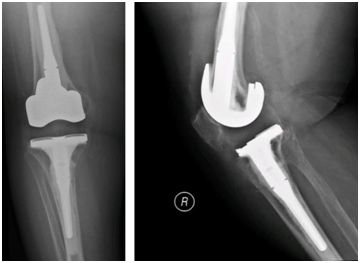

The patient was started on antibiotic treatment with doxycycline for six months plus rifampicin and streptomycin for three weeks. After two months, the patient had a second-stage total knee replacement (Figure 2). After surgery, she was discharged on streptomycin and rifampicin. In her three-year follow-up, the patient was doing fine, she had a full 0 degree of right knee extension and 100 degrees of flexion, walks with a cane as a baseline after her spine surgery, and had no signs of prosthetic failure (Figure 3).